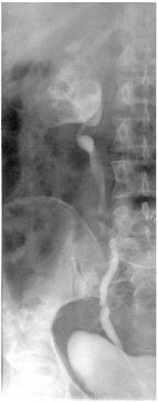

Донорские почки могут быть успешно пересажены, даже если существует сильная несовместимость ткани между донором и реципиентом. Междисциплинарная рабочая группа, возглавляемая доктором Кристианом Морэтом, старшим консультантом в Отделении Нефрологии в Гейдельбергской Университетской клинике (Медицинский директор: профессор доктор Мартин Зеир), и профессор доктор Кэнер Сузэл, глава лаборатории антитела в Отделении Трансплантационной иммунологии, показал в исследовании 34 чувствительных рискованных пациентов, что показатель успешности в этих пациентах не отличался от показателя успешности пациентов с низким иммунологическим риском. …